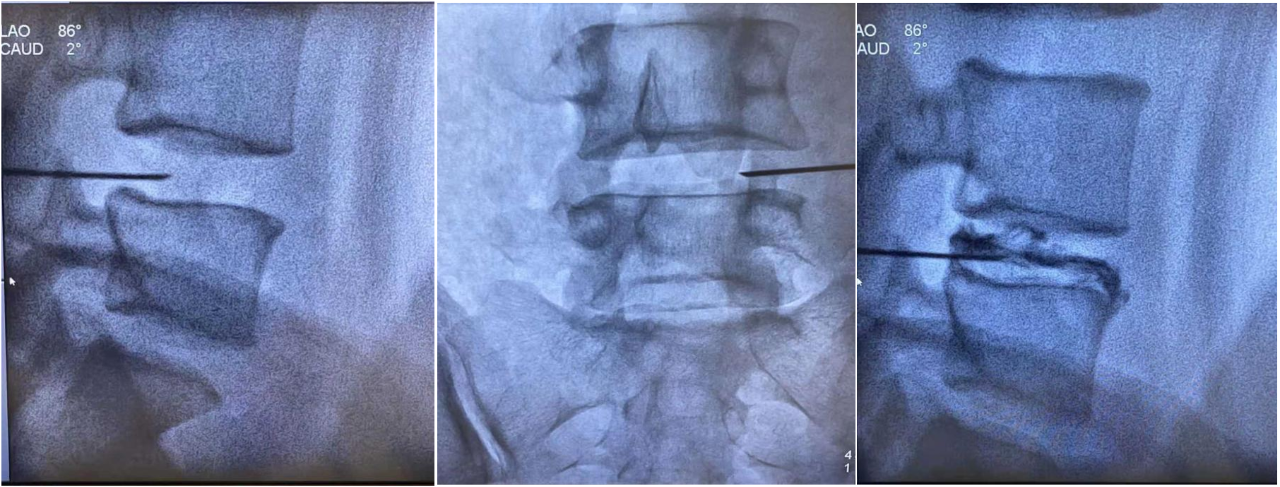

手術歷時1個小時20分鐘,術中完全復制疼痛癥狀,精準消融,術后白女士恢復良好。

該手術創口只有約0.1~0.2mm的針眼,x線引導下精準穿刺間盤,術中通過責任間盤的造影復制癥狀,低溫等離子消融髓核、滅活生長入破口處的竇椎神經,達到消除疼痛,改善癥狀的作用。